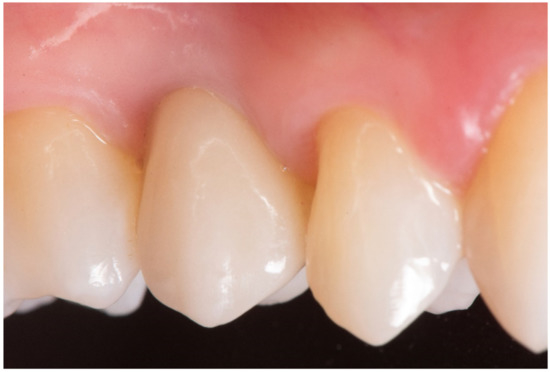

Implant Placement Following Crestal Sinus Lift with Sequential Drills and Osteotomes: Five Years after Final Loading Results from a Retrospective Study

3. Results

| Survival rate | 98.1% | 98.1% |

| Complications | BOP at 2 implants | None |

| Marginal Bone loss | 0.94 ± 0.18 mm | 1.24 ± 0.28 mm |